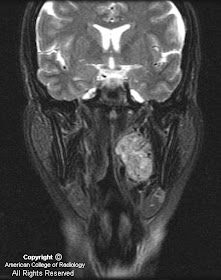

Figure 1 demonstrates a large, intensely-enhancing, heterogeneous left-sided carotid space mass displacing the internal carotid artery (ICA) medially, the external carotid artery (ECA) and its branches antero-medially, and the internal jugular vein (IJV) postero-laterally.

Paragangliomas account for only 0.6% of all neoplasms of the head and neck. They arise from the paraganlgia or glomus cells, which are part of the extra-adrenal neuroendocrine system, and are named for the paraganglia from which they arise. The four most common sites for paragangliomas of the head and neck are the carotid body (carotid body tumor), the jugular foramen (glomus jugulare), along the path of the vagus nerve (glomus vagale) and in the middle ear (glomus tympanicum). Paragangliomas are characteristically vascular, intensely enhancing lesions that demonstrate low T1 and high T2 signal with multiple flow voids. The "salt-and-pepper" appearance has been named for the T2 appearance, as the high T2 signal of the tumor is the "salt" and the multiple flow voids the "pepper".

Paragangliomas can be distinguished from each other primarily based on their location. The carotid body tumor typically splays the common carotid bifurcation, while the glomus vagale displaces both the ECA and ICA antero-medially away from the IJV. Glomus jugulare tumors characteristically expand and erode the jugular foramen causing the characteristic "moth-eaten" appearance. The glomus tympanicum is a small discrete mass arising from the cochlear promontory in the middle ear.